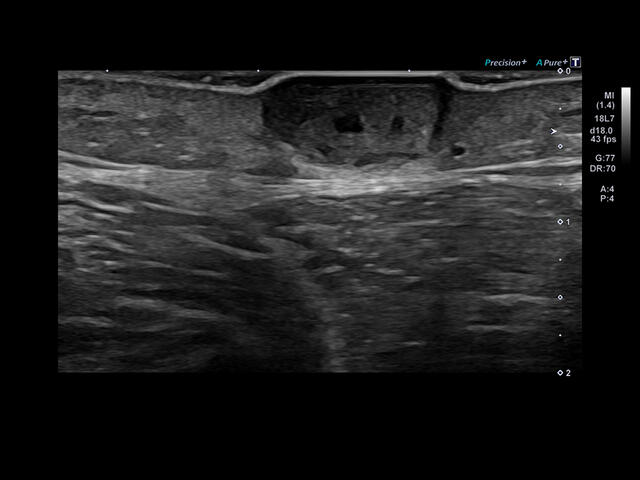

Уровень сосудистой визуализации SMI в сочетании с высокой частотой кадров повышает диагностическую достоверность при оценке поражений, кист и опухолей.

SMI с цветовой кодировкой позволяет одновременно отображать информацию о потоках и оттенках серого с высокой временной и пространственной информацией.